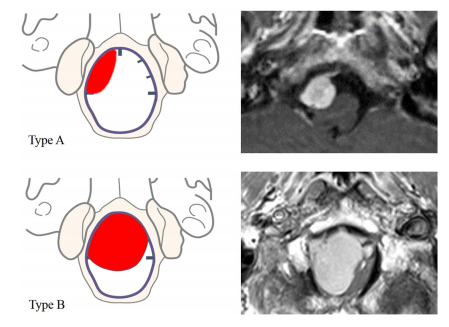

考虑到硬脑膜轴向附着与齿状韧带的关系,前病变33例(84.6%),后病变6例(15.3%)。我们进一步将前病变内的硬脑膜附着区分为8个单纯的前外侧病变和25个前外侧病变。前外侧肿瘤分为A型12例和B型13例。

图1(A,B)不同类型的前外侧脑膜瘤:A型,侧位总患病率,硬膜附着不超过中线,B型,中线两侧有不同程度的硬脑膜附着

图5(左)和T1加权磁共振图像的两个治疗病例(右)显示的例子,两个不同的轴向平面位置的肿瘤。完全在一侧,没有超出中线的延伸(A型)和中线两侧的硬脑膜附着物(B型)